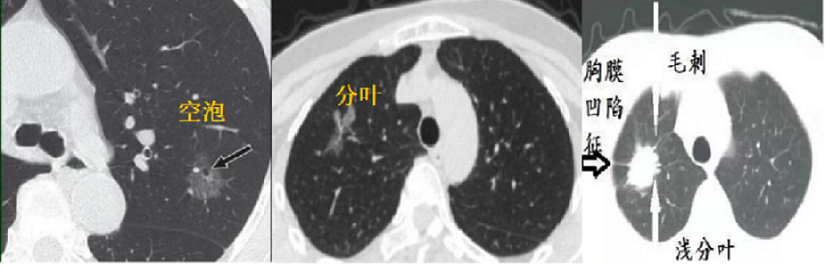

3、病灶形态。空泡型GGO、有分叶或毛刺、胸膜凹陷、血管集束及支气管充气等征象时恶性可能性大。

图五 恶性病灶影像学表现